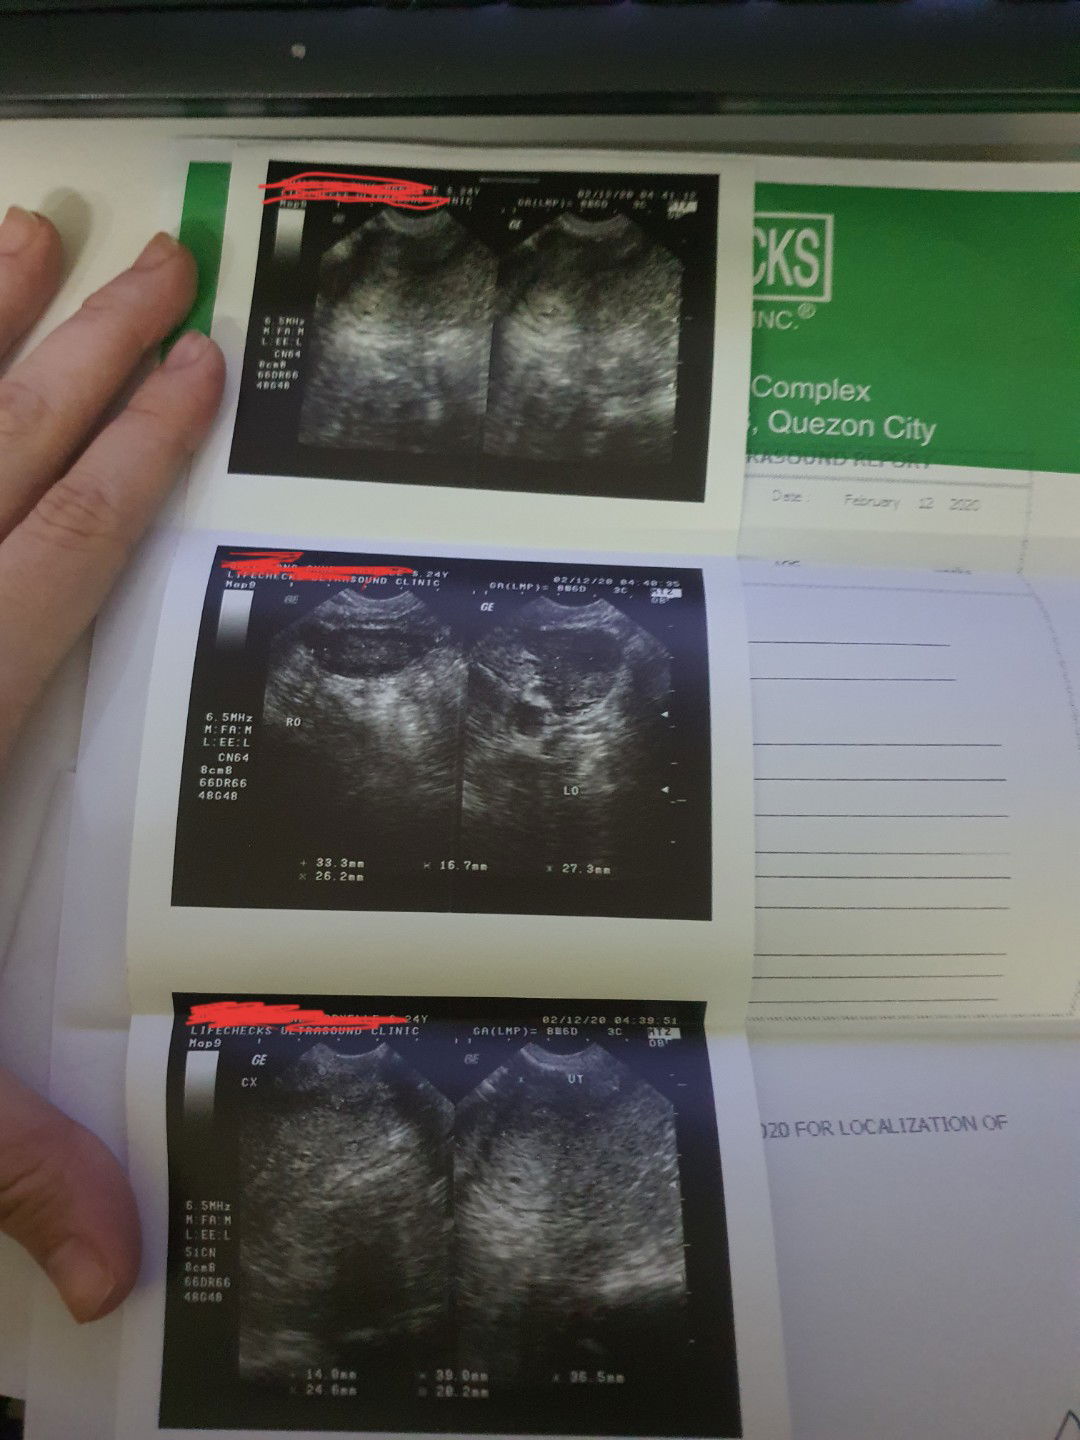

Hi mga mommies! I am 2 months delay already. My last menstruation was December 12. My PT shows positive last Feb 8. But this afternoon, I went to the doctor to confirm pero sabi niya maliit pa daw and hindi pa confirmed so she has prescribed Duphaston and BioFolate and come back after 2 weeks. May pagasa pa ba to mga mommies? And also ano mairerecommend niyong mga dapat kong kainin or what. First time mom to be here. Thank you